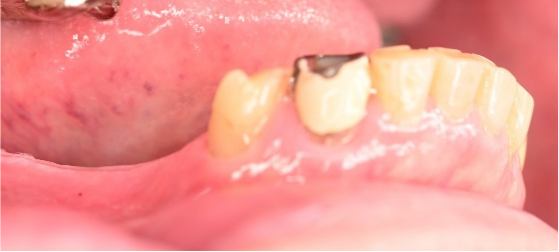

Before

▼初診時に使用していた部分入れ歯を装着したところ

▼インプラント埋入前